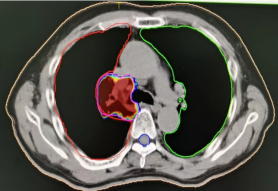

1、肺癌横断面及矢状面肿瘤处治疗剂量显示图

3、计划系统效果图:黄色线内-蓝色线外深颜色区域为高剂量区域,黄色线外及蓝色线内为低剂量区域。即照射剂量区域可按肿瘤治疗的需要进行调节。